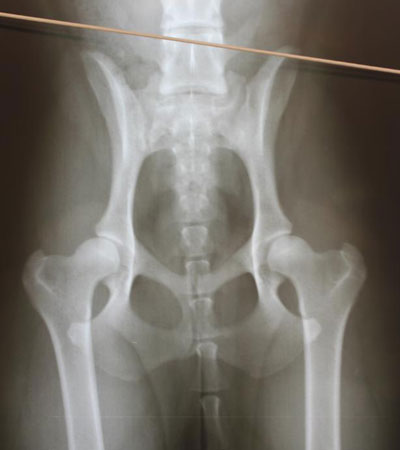

Tarana B/B

Scored in Finland